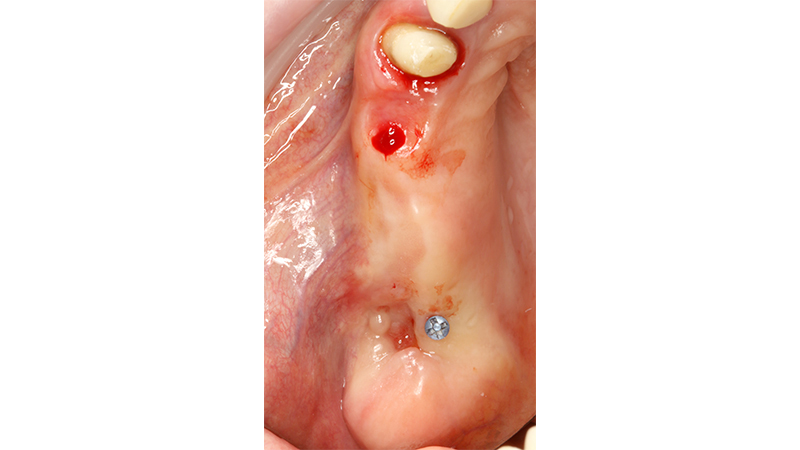

Sul 12 veniva eseguito un impianto post-estrattivo con carico immediato mediante moncone conometrico e provvisorio ricavato ribasando una cappetta provvisoria in peek e applicazione a frizione mediante conometria (Figs. 19, 20, 21, 22, 23).

Carico immediato su 12 con moncone conometrico dritto e cappetta provvisoria in peek ribasata in resina su provvisorio. Foto dopo l'intervento con esecuzione flapless e leggera plastica gengivale del Tuber applicazione di cappette di guarigione in peek. Guarigione dei tessuti dopo 3 mesi e impronta digitale definitiva per finalizzare il caso

Fig. 19, 20 - Carico immediato su 12 con moncone conometrico dritto e cappetta provvisoria in peek ribasata in resina su provvisorio. Foto dopo l'intervento con esecuzione flapless e leggera plastica gengivale del Tuber applicazione di cappette di guarigione in peek. Guarigione dei tessuti dopo 3 mesi e impronta digitale definitiva per finalizzare il caso

Fig. 21 - Carico immediato su 12 con moncone conometrico dritto e cappetta provvisoria in peek ribasata in resina su provvisorio. Foto dopo l'intervento con esecuzione flapless e leggera plastica gengivale del Tuber applicazione di cappette di guarigione in peek. Guarigione dei tessuti dopo 3 mesi e impronta digitale definitiva per finalizzare il caso

Fig. 22 - Carico immediato su 12 con moncone conometrico dritto e cappetta provvisoria in peek ribasata in resina su provvisorio. Foto dopo l'intervento con esecuzione flapless e leggera plastica gengivale del Tuber applicazione di cappette di guarigione in peek. Guarigione dei tessuti dopo 3 mesi e impronta digitale definitiva per finalizzare il caso

Fig. 23 - Carico immediato su 12 con moncone conometrico dritto e cappetta provvisoria in peek ribasata in resina su provvisorio. Foto dopo l'intervento con esecuzione flapless e leggera plastica gengivale del Tuber applicazione di cappette di guarigione in peek. Guarigione dei tessuti dopo 3 mesi e impronta digitale definitiva per finalizzare il caso